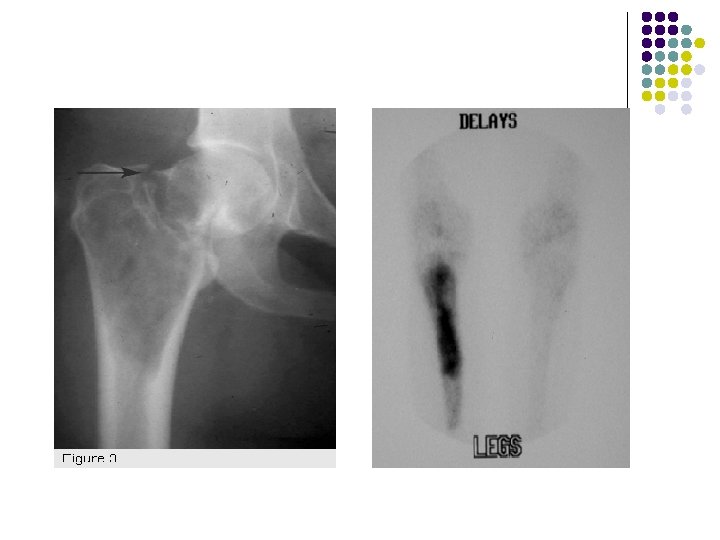

PLAIN RADIOGRAPH l l l l Expansile , Solitary lytic bone lesion Closed epiphyses No reactive sclerosis /No periosteal reaction May break through cortex with cortical thinning Soft-tissue invasion (25%) Pathologic fracture (5%) May cross joint space in long bones (exceedingly rare)

CT: l Tumor has soft-tissue attenuation (May contain foci of low attenuation (hemorrhage/necrosis) l Well-defined margins WITHOUT rim of sclerosis MRI l Heterogeneous signal intensity with low to intermediate intensity on T 1 WI & T 2 WI due to collagen and hemosiderin content.

Axial ct of proximal leg-Soft tissue attenuation with well defined margins and foci of low attenuation within due to h’age or necrosis. Coronal CT scan of a giant cell tumor of the distal ulna show soft tissue attenating lesion.

NUCLEAR MEDICINE IMAGING l Diffusely increased uptake l May have "doughnut" sign of central photopenia (cold lesions with increased uptake around the rim) ANGIOGRAPHY: Hypervascular lesion

Bone scintigraphy shows hyperconcentration of tradiotracer in diastal radius due to GCT